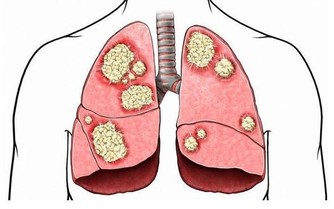

魚際穴:手中的「保命穴」 在手掌大拇指根部和手腕連線中點,有一個穴位,這就是魚際穴。 中國中醫科學院西苑醫院老年病中心教授李躍華表示,別小看了這個穴位,它可有著「保命穴」之稱,多按摩魚際穴對健康大有好處。 1、中醫認為魚際穴化肺經水濕,散發脾土之熱,可緩解呼吸系統疾病,如感冒、支氣管炎、肺炎、咽炎等。 2、老人常出現小便短少的情況,也可以對魚際穴進行敲擊,從而得到緩解。 3、按摩魚際穴,對因過度使用電子產品造成的「滑鼠指」有很好的治療作用。 4、魚際穴配合按摩其他穴位,還能治療咳嗽、咽喉腫痛、口乾舌燥等。